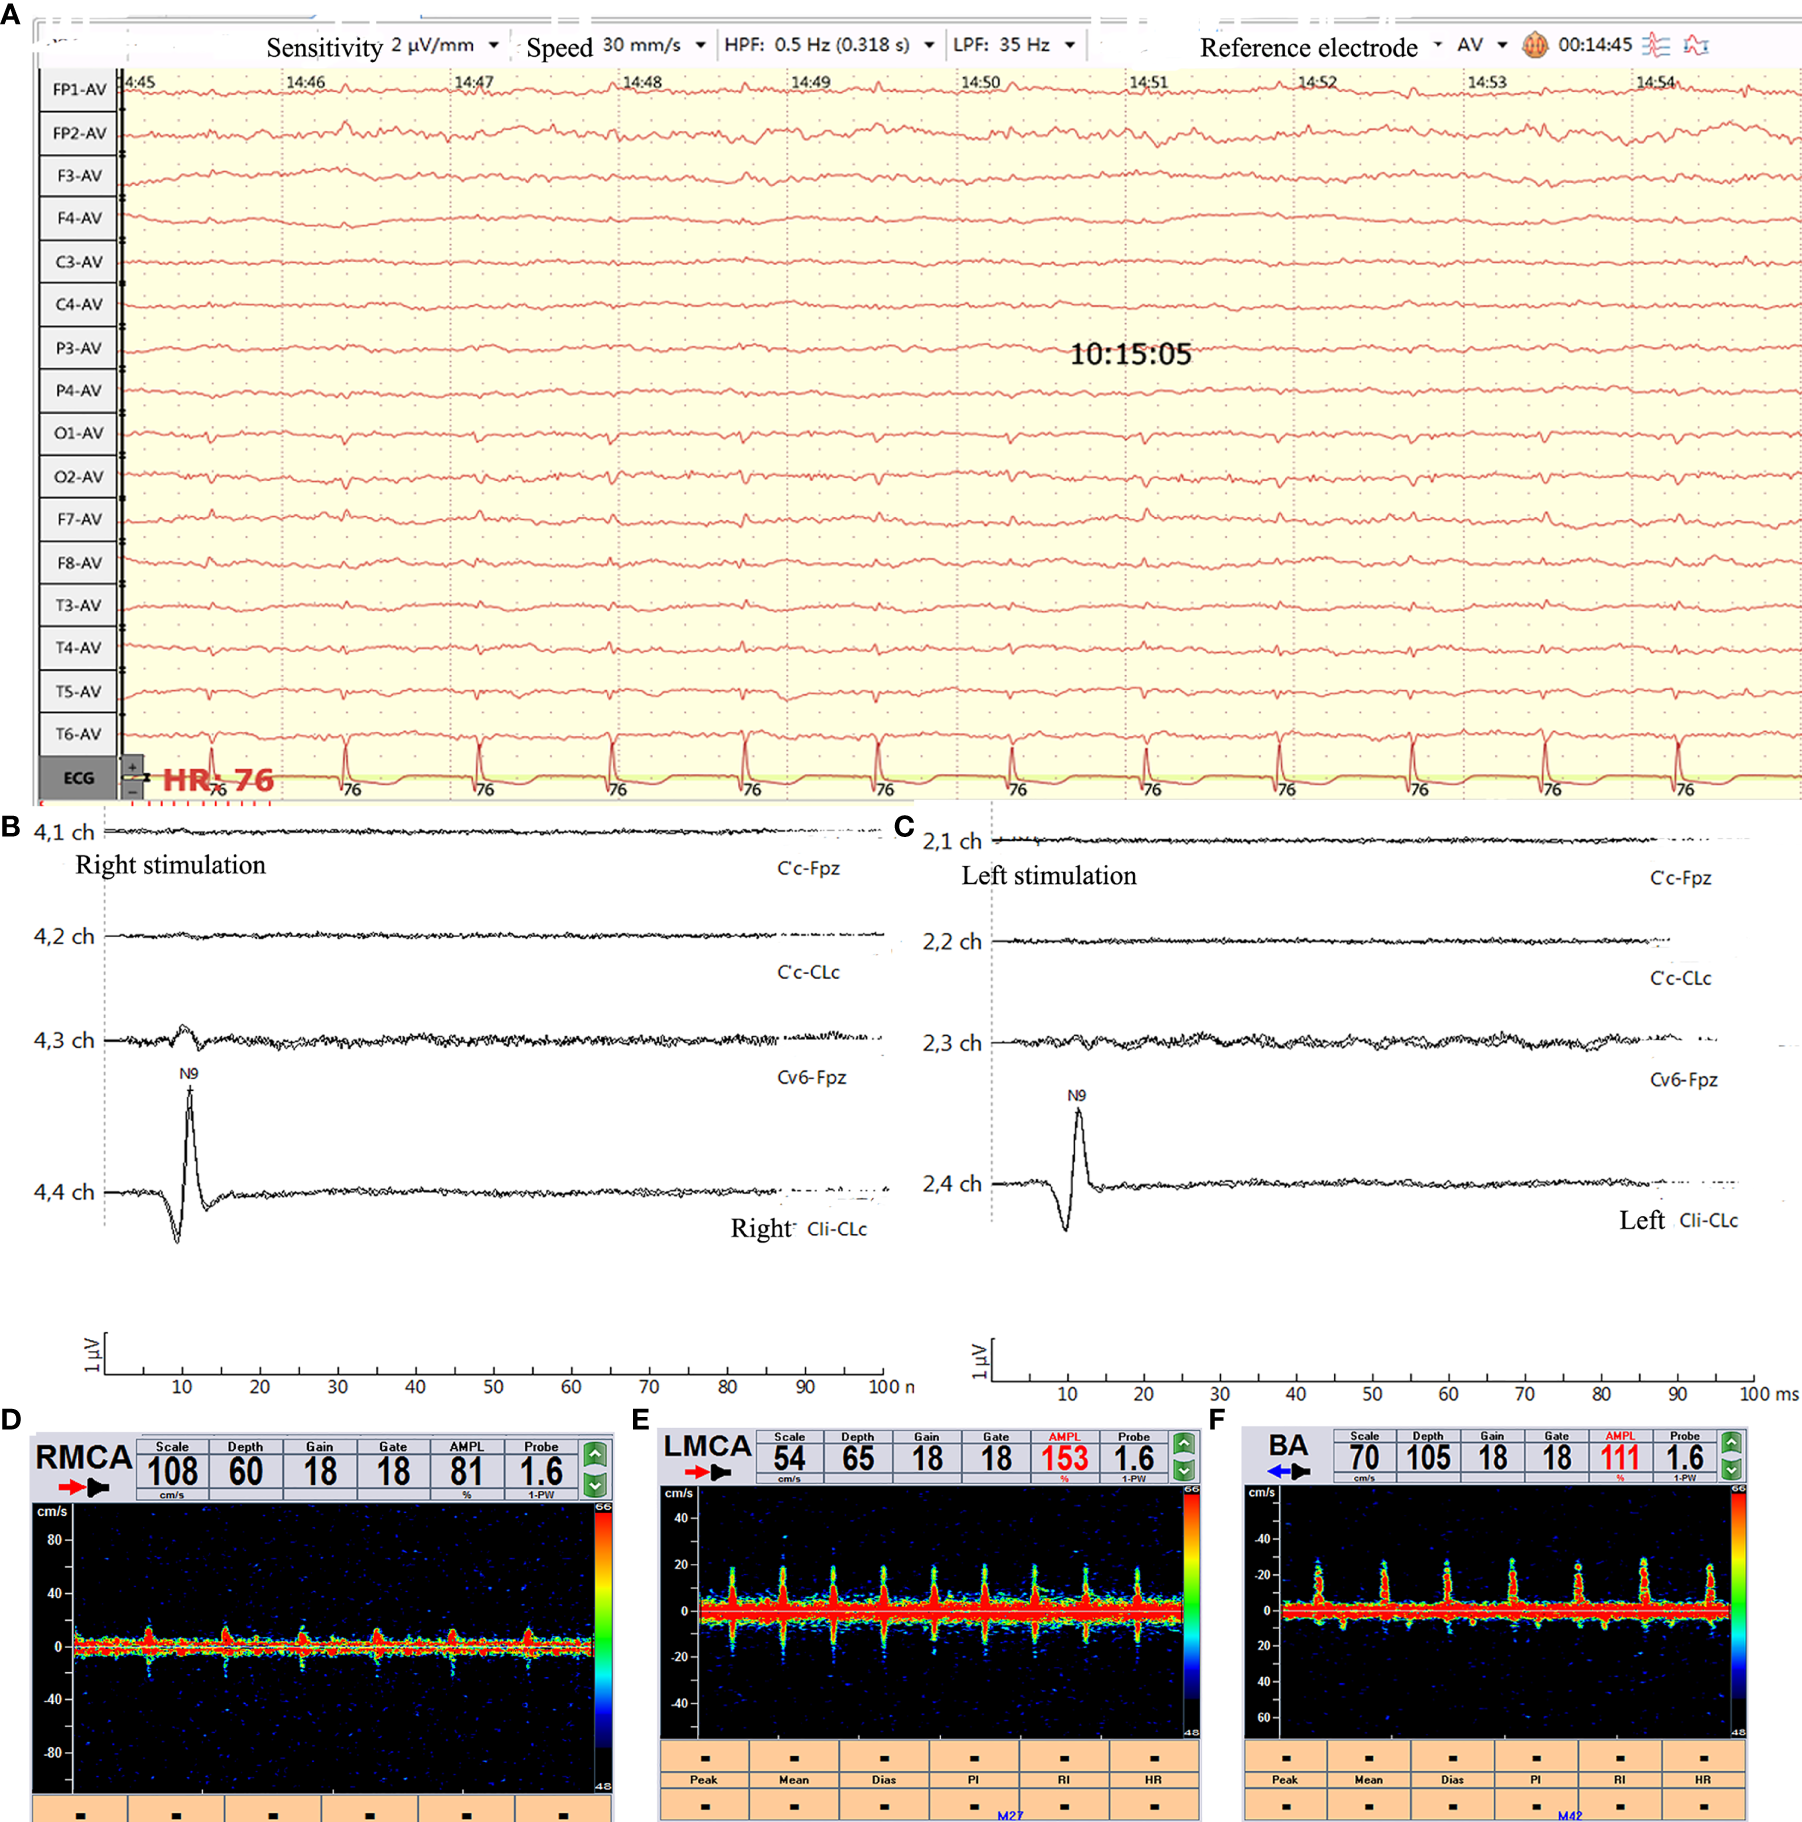

He was administered 6.0 g/d meropenem (2.0 q8 h iv-vp), 2.0 g/d vancomycin (0.5 q6 h iv-vp) and 10 mg/d dexamethasone. However, his condition remained deteriorated. On the night of admission, his other pupil was also enlarged (5 mm) without light reflection, and his other brain stem reflexes disappeared. Two days after admission, the electroencephalogram (EEG) showed a low wave (Figure 2A), and the TCD showed a sharp small wave in the right middle cerebral artery (RCMA)/left middle cerebral artery (LCMA)/basilar artery (BA) (Figures 2D–F). Moreover, his blood pressure dropped below 60/30 mmHg, and his sodium levels increased from 132 to 195 mmol/L in 24 h. The patient began to produce urine at 300 ml/hour, and as the sodium level increased, the serum osmolality increased sharply, and the urine volume dropped from 7200 ml/day to less than 1000 ml/day. Then, his creatinine(CREA) level gradually rose to 350 µmol/L. He experienced hyperpotassemia. In addition, continuous renal replacement therapy (CRRT) was applied discontinuously, after which his sodium levels decreased from 195 to 145 mmol/L and his urine output was maintained at approximately 2000-3000 ml/day. The potassium ion level dropped from 8.1 mmol/L to a normal level.

Figure 2

Brain function evaluation. (A) Video-EEG recording (international 10-20 system using the average reference electrode, over half an hour) showed that the wave amplitude was lower than 2 µv. (B, C) SSEP showed bilateral N9 normal and N13/P14/N18/N20 disappeared. (D–F) TCD showed sharp small waves or nail-like waves in RCMA/LCMA/BA. RCMA, Right middle cerebral artery; LCMA, Left middle cerebral artery; BA, basilar artery.

When his Na+ concentration returned to normal, somatosensory evoked potential (SSEP) analysis showed that the bilateral N13/P14/N18/N20 disappeared (Figures 2B, C). A computed tomography (CT) scan of the brain showed a diffuse subarachnoid hemorrhage (Figures 1C, D). His clinical features indicated brain death. However, the relatives of the patient did not want to give up, and he was administered amphotericin B liposomes (10 mg-20 mg-40 mg-60 mg/d). During hospitalization, he suffered from severe damage to the liver and kidneys and electrolyte disorders that required CRRT. He died after 3 months. The timeline with relevant data from the episode of care was showed as Figure 4 (supplement).